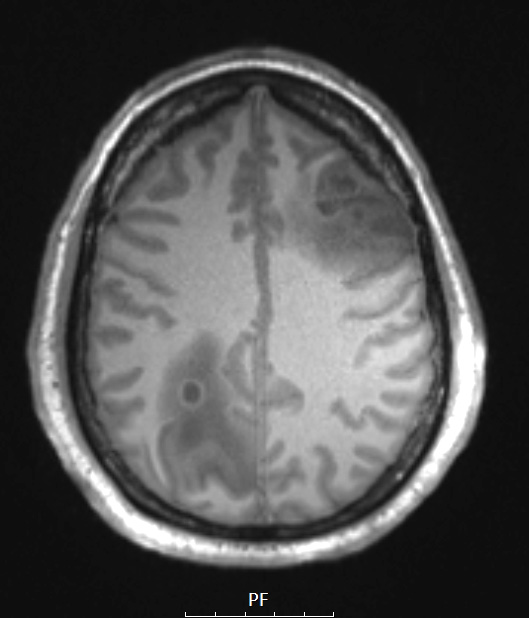

A T1 weighted MRI scan without contrast shows prominent perilesional edema.